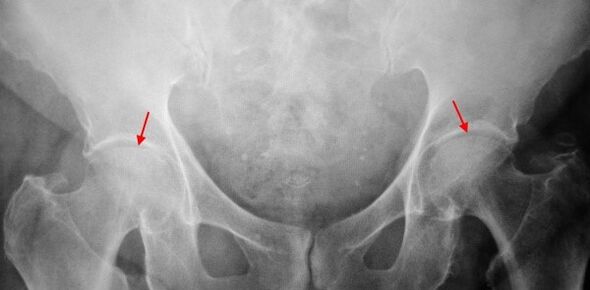

In the x -Ray patients suffering from coxarthrosis in the first stage, mild changes are determined: uneven narrowing of the joint gap, as well as bone growth around the external or internal edge of acetabulum if there is no change from the head and neck of the femur.

In image X -ray for the 2nd degree coxarthrosis, uneven narrowing of the joint gap (more than half of normal height) is determined.The femoral head is slightly turned upwards, defects and increases in size, and the contour becomes uneven.Bone growth with this level of coxarthrosis not only appears internally, but also on the outer edge of acetabulum and goes outside the cartilage.

On radiography for the 3rd degree coxarthrosis, sharp narrowing of the joint gap, significant thigh head development and double bone growth are detected.

The diagnosis of coxarthrosis is based on clinical signs and additional study data, the main is radiography.In many cases, the X -Rays allows it to create not only the level of coxarthrosis, but also the cause of its occurrence.So, for example, an increase in the neck-dappyseal angle, scenes and leveling acetabulum indicate displacement, and changes in the form of femur proximal parts indicate that coksartrosis is a result of pertes or young epiphysiolysis.In radiography of patients with coxarthrosis, changes can also be detected indicate injury.